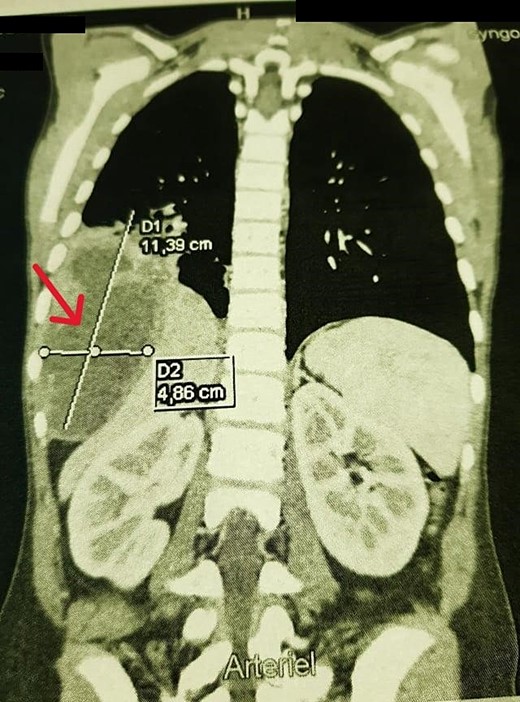

A chest X-ray demonstrated right hemi-diaphragmatic elevation. Given this finding, a computed tomography scan (CT) of the chest and abdomen was performed for further evaluation. The CT report concluded the presence of a hydatid cyst originating from the hepatic dome with a suspected intrathoracic extension (Figs 1 and 2). Serological testing for echinococcosis was positive.

Coronal chest CT view 11 × 4 cm2 hydatid cyst that seems arising from the liver with possible intrathoracic rupture.